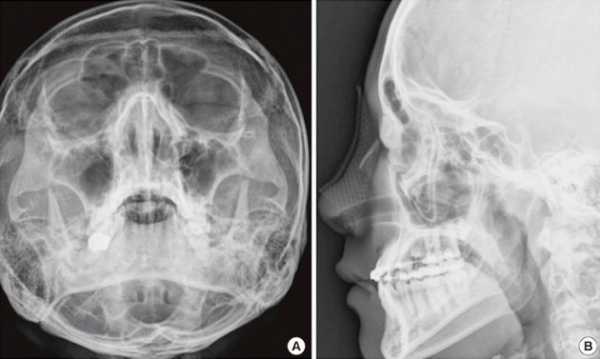

Чтобы оценить, какова степень тяжести повреждения, прежде всего делают рентгеновский снимок. Такое исследование (помимо уточнения характера перелома) позволит определить, сопровождается ли полученная травма повреждением черепа. Если рентгенограмма фиксирует явные дефекты костей носа и лицевого черепа, то это является прямым показанием для хирургической коррекции повреждений. Если причиной перелома была тяжелая травма головы, то назначается компьютерная томография для выявления возможных повреждений головного мозга.

В настоящее время наиболее информативными являются инструментальные методы диагностики перелома носа. Например, такие как:

- рентгенография;

- компьютерная томография;

- эндоскопический осмотр.

Рентген детально позволяет устанавливать при сломанном носе степень повреждения костей и тяжесть болезни. Перелом носовой кости — это минимальное повреждение.

При помощи рентгенографии врач определяет линию перелома, оценивает смещение костных носовых отломков, определяет наличие отломков носа в мягких тканях.

При переломе носа рентген выполняют в двух проекциях – боковой и прямой. Такой способ диагностики наиболее информативен в первые часы после перелома.

Компьютерная томография дает более точную информацию и линиях перелома носа, возможном смещении костных носовых отломков.

При этом можно выявить повреждения глазниц, носовых пазух и костей черепа.

- В больнице после осмотра и проведения рино- или эндоскопии (инструментальный осмотр полости носа) лор должен назначить больному рентгенограмму костей носа. На основании этих исследований ставится диагноз, и если нужна операция, намечается ее стратегия. Если отек носа еще не успел развиться, операцию лучше провести немедленно. Если же налицо отек, то пострадавшего на недельку отправят домой.